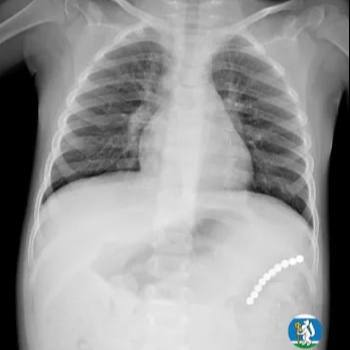

Ульяна почувствовала себя плохо, и родители отвели её к медикам. Те сначала думали о пневмонии. Сделали рентген и на снимке увидели, что в желудке застряла цепочка из магнитных шариков.